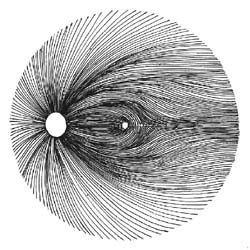

Kdybychom tak uměli spočítat množství gangliových buněk jako umíme změřit nitrooční tlak! To by se nám diagnostikoval glaukom! Na množství gangliových buněk můžeme jen usuzovat podle svazečků nervových vláken na sítnici a podle šíře neuroretinálního lemu terče zrakového nervu. Sledování změn vrstvy nervových vláken je citlivější pro včasné poznání glaukomu než sledování terče samotného. Vzhledem k variabilitě terče je obtížné stanovit jednotnou normu pro všechny lidi. Vrstva nervových vláken morfologicky je však téměř stejná u každého člověka!